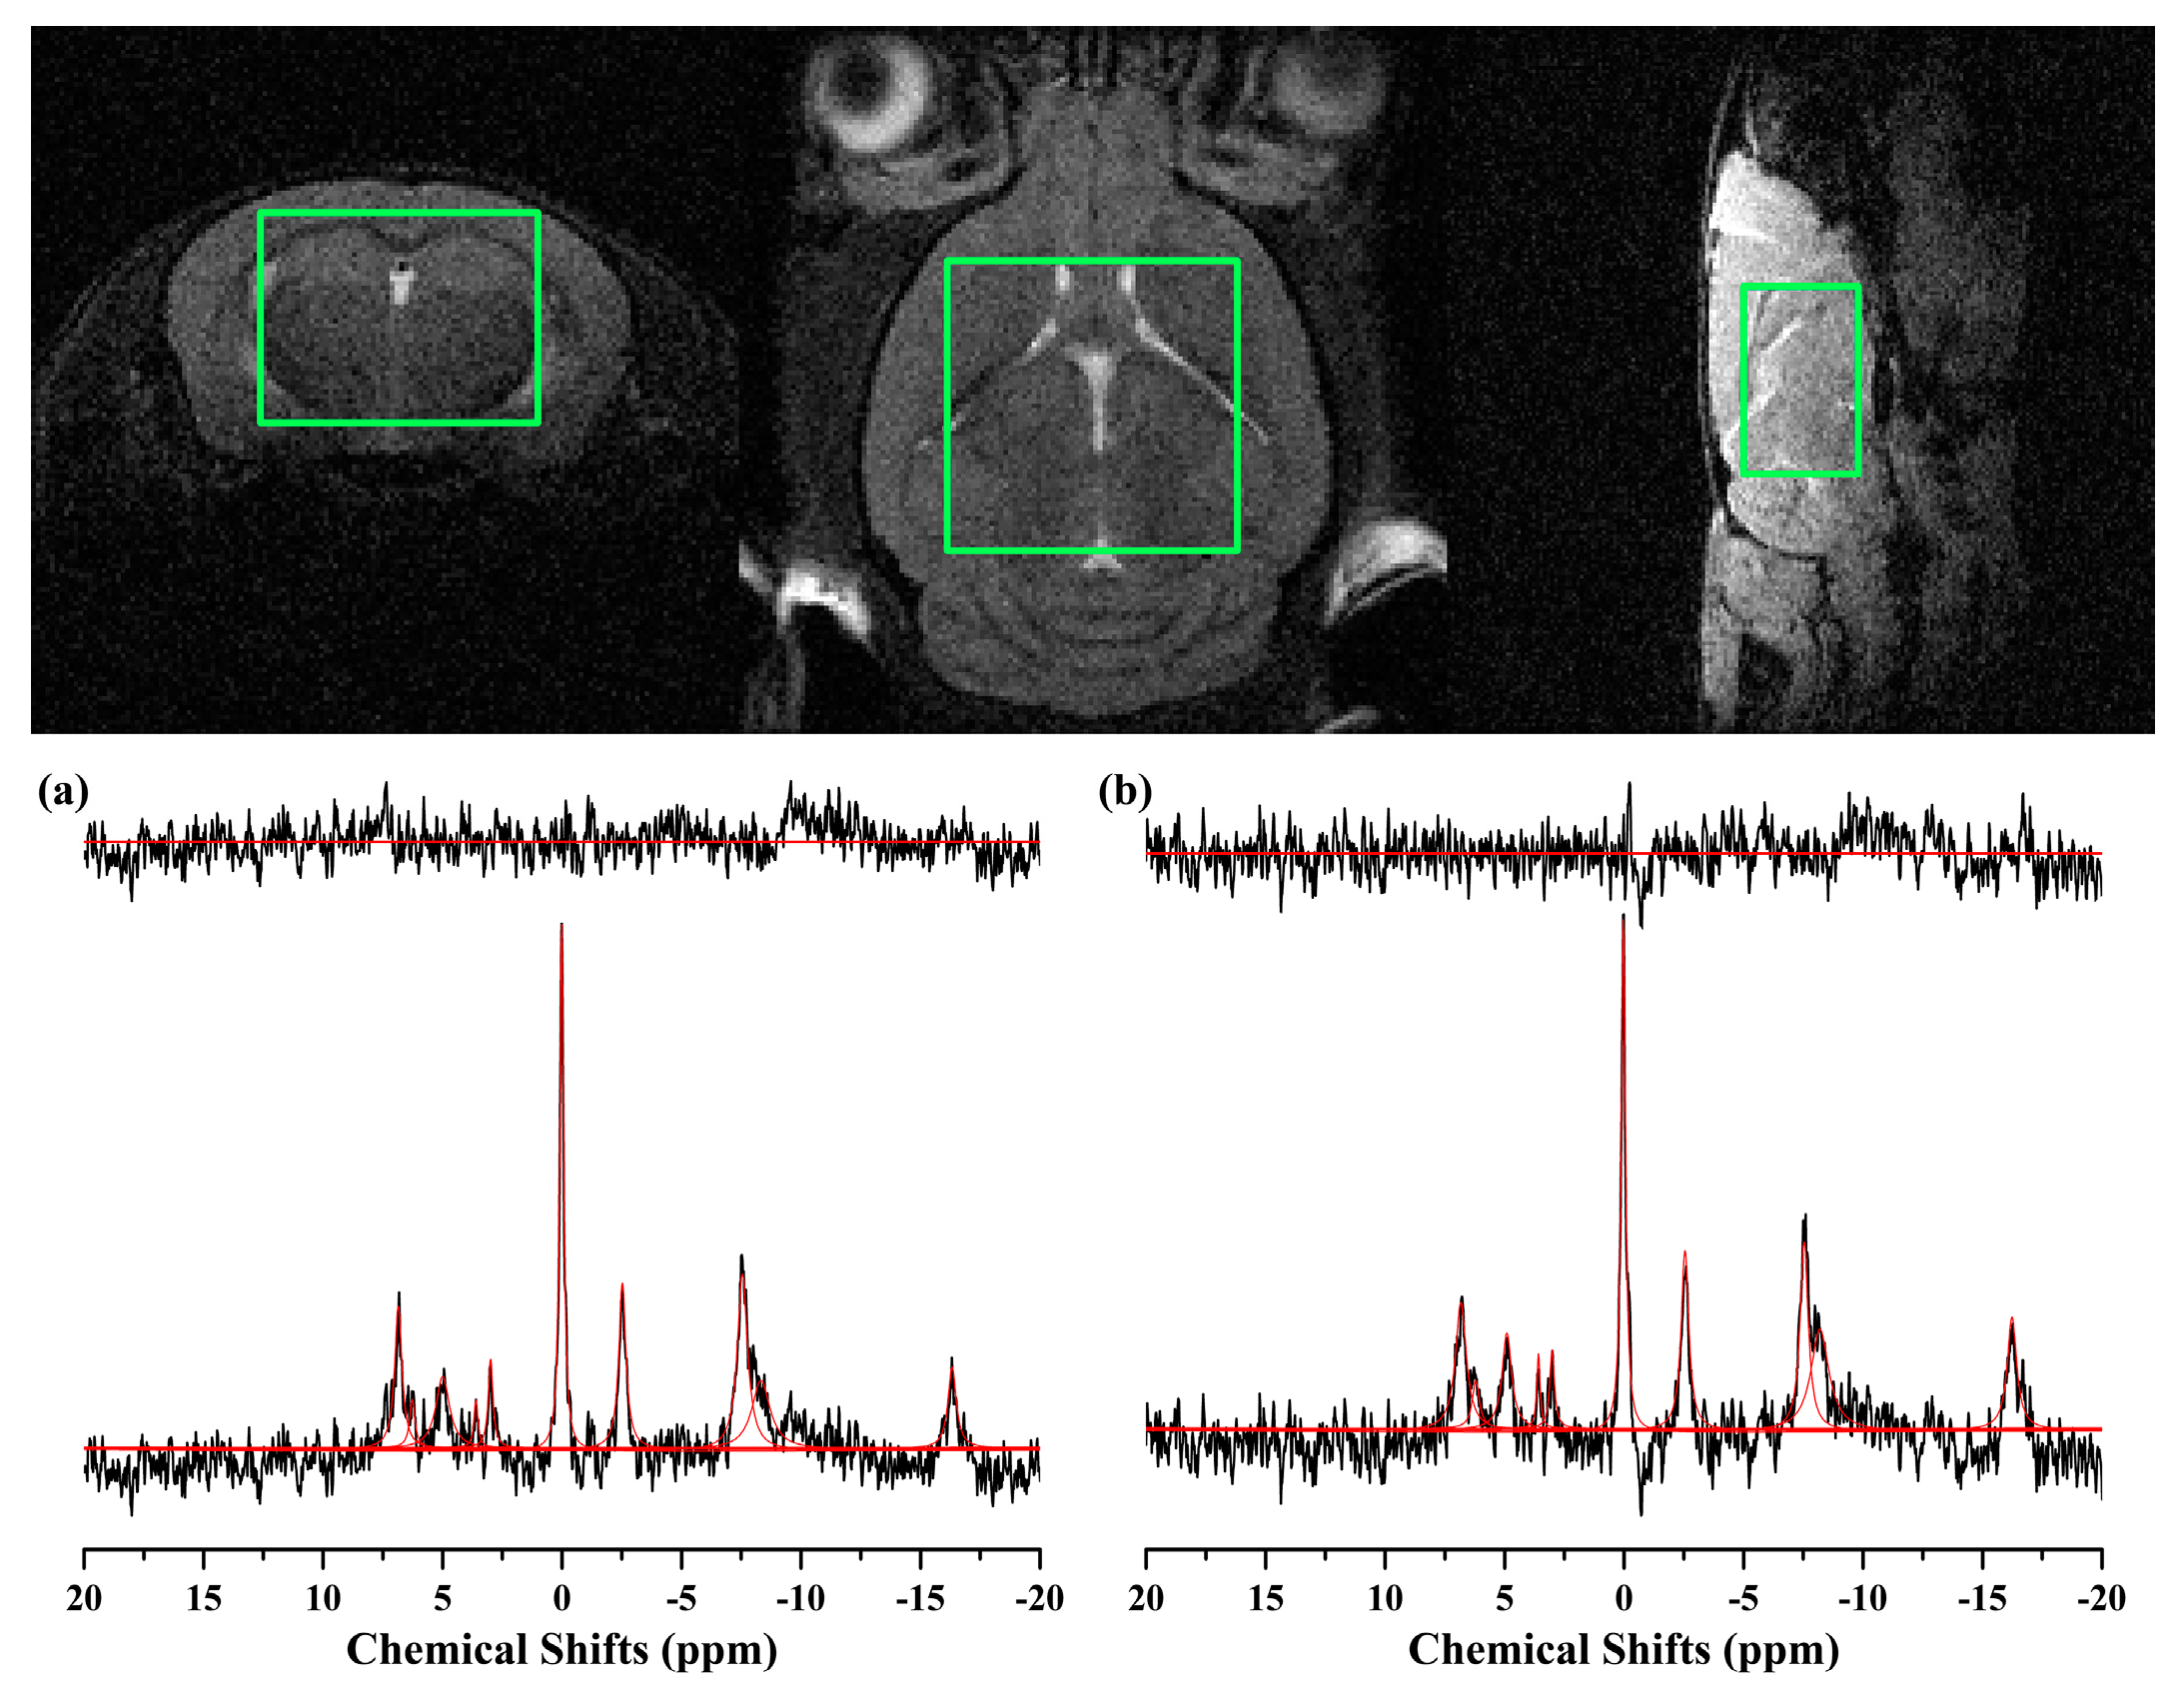

Figure 4 illustrates 31P MRS scans obtained in the whole brain region of the 11-month-old (a) 5xFAD and (b) WT mice. The PCr peak was at the center of the frequency range, and all peaks of the individual metabolites can be identified. Table 2 lists the/PCr of the metabolites from the 5xFAD (n = 7) and WT mice (n = 5). Statistically significant decreases in NADP and PME/PDE ratio were observed in the 5xFAD mice compared to WT (p < 0.050).

Figure 4.

Representative 31P MRS scans, obtained using ISIS sequence with the following parameters: TR = 4000 ms; complex data points = 4096; average = 128 (1024); spectral bandwidth = 16,025.64 Hz. Scans in the whole brain of mice (7.0 × 4.0 × 7.0 mm3; green box) of the (a) 5xFAD and (b) WT mice at 11 months of age were illustrated as the raw spectra (black), fitted spectra (red), spectra baseline (blue), and residual error (top). Phosphorus magnetic resonance spectroscopy, 31P MRS; image selected in vivo spectroscopy, ISIS; repetition time, TR.

Localized in vivo 31P MRS scans were acquired in the whole brain of mice, as shown in Figure 4. Although some previous 31P MRS studies have revealed significant changes in high-energy phosphate, such as, ATP, PCr, or Pi level in the various regions of the AD brain [13,14], conflicting results have been reported [41]. In this study, no significant changes were observed in these metabolites, ATP/PCr or Pi/PCr, consistent with the previous studies [31,41]. Similar to the previous findings, this result may reveal that a significant depletion in brain energy stores, chronic hypoxia, nor ischemia has occurred in the brain of 5xFAD mice [31]. Decreased PME with elevated PDE in 5xFAD mice was consistent with the previous study, which reported a significant decrease of PME and an increase of PDE in bilateral hippocampi of mild cognitive impairment and AD subjects compared to control subjects [42]. Moreover, previous studies reported that the alteration in brain PME and PDE levels varies according to the progress of AD [14,15]. In the early stage of the AD brain, PME levels were reported to be increased [15], while in the progressed AD brain, PDE was elevated in the brain [14]. The 5xFAD mice in this study is known to resemble the progressed AD. Thus, the alteration of PME and PDE levels in the 5xFAD mice brain is consistent, at least partially, with this previous clinical findings [14]. Considering their roles, decreased PME and elevated PDE indicate a disruption in the membrane synthesis and elevation of breakdown in the brain of 5xFAD mice [14,42]. Significant reduction in NADP in the brain of 5xFAD mice can be interpreted that the redox status being increased, considering that the most critical function of NADP is to counteract oxidative damage and to maintain a pool of reducing equivalent essential for other detoxification reactions [43].